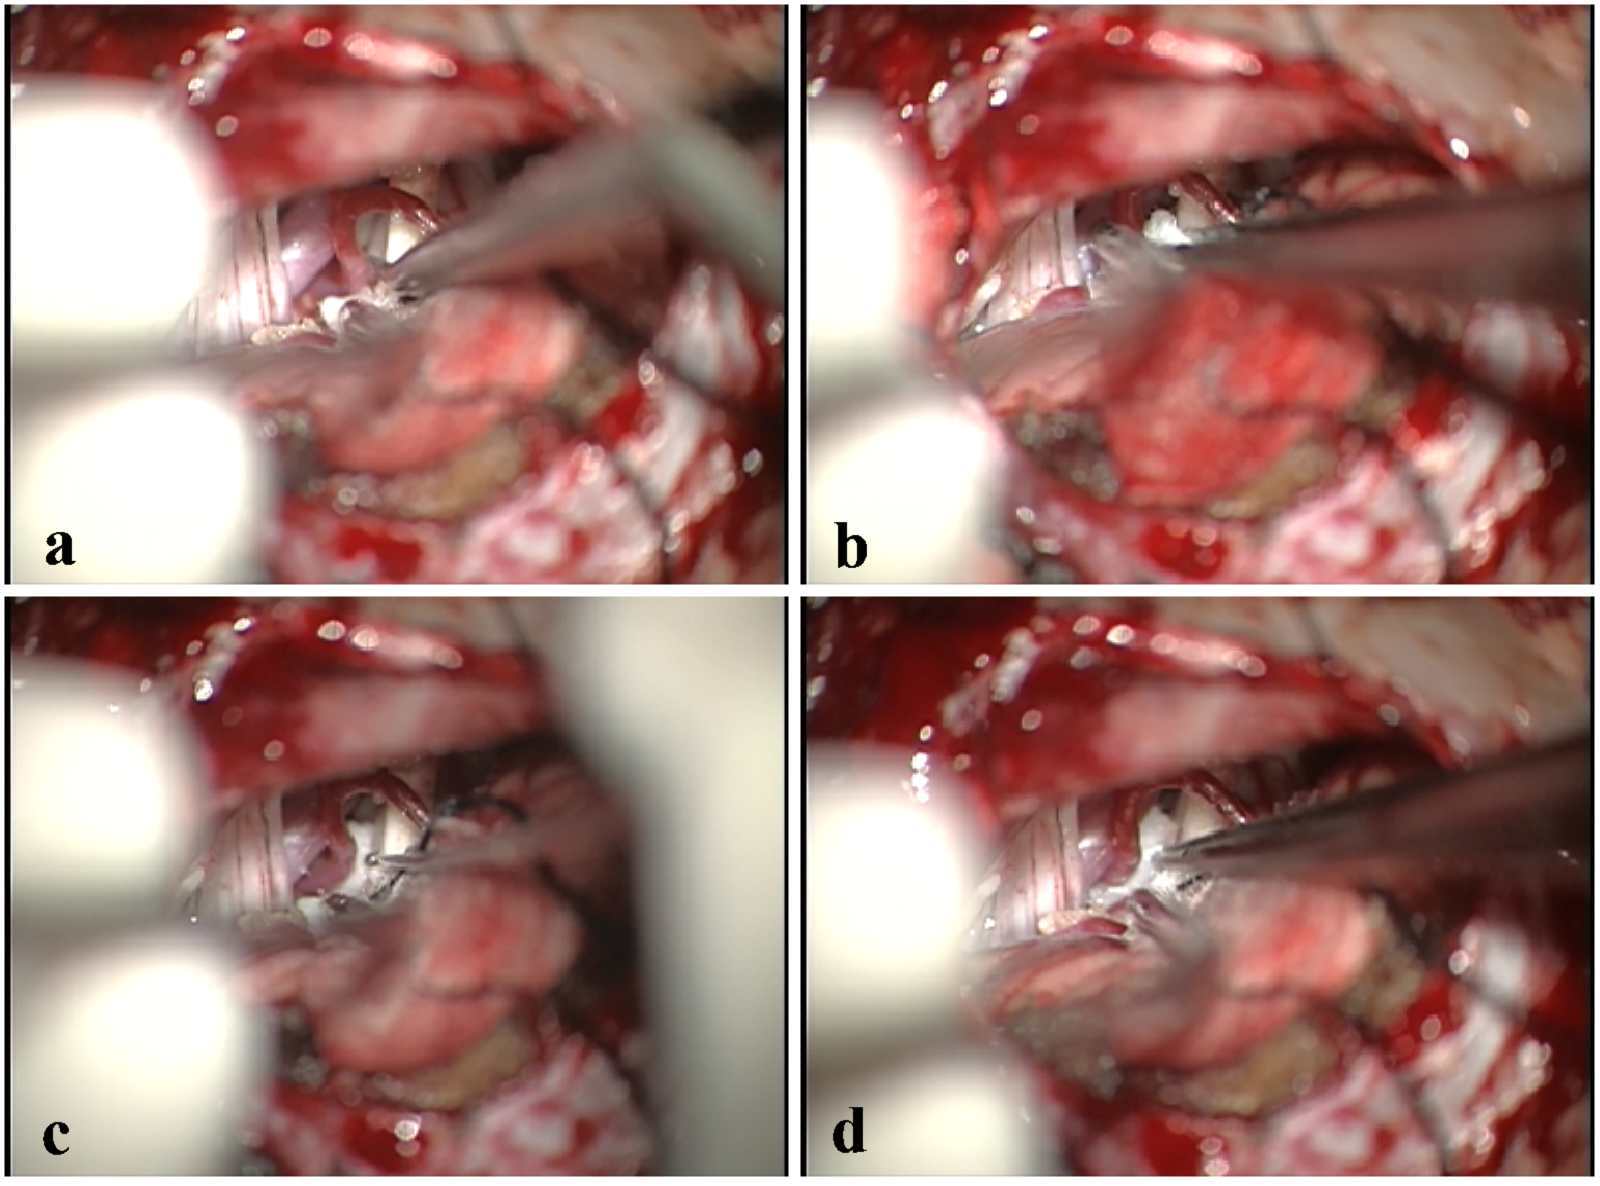

经颅后窝面神经微血管解压术因其疗效确切,不易复发,极少造成面部感觉障碍,并且随着手术显微镜的发展,其出现并发症的几率很低,而越来越为更多的患者所接受。该类手术的核心原理是:在手术显微镜下微创操作,分离压迫面神经根部的血管襻,然后插入特制的垫片将血管与神经隔离开来,彻底去除了血管对面神经的压迫,解除了患者的痛苦,是目前国际上公认的面肌痉挛疾病最有效方法。微血管减压术,其治疗面肌痉挛的总有效率为90%,且复发率低,为面肌痉挛患者带来了曙光。

术中过程